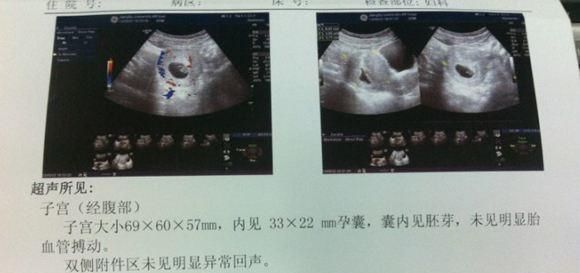

怀孕45天之后建议做B超检查

大多会写着宫内早孕,单活胎这样的报告是正常的,说明没有宫外孕,是在宫内妊娠,而且只有一个胎儿就是单胎,看到胎囊,胎芽和胎心。

这时候如妈太胖的可能通过腹部看不清,可以考虑做阴超,也就是阴部B超。万一孕7周看不到胎心搏动的,一般还要在孕8周再进行检查,可能就看到胎心了。